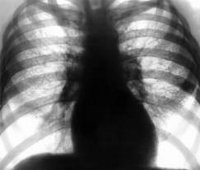

Рентгенография грудной клетки

Рентгенограмма грудной клетки. Рентгенологическое исследование, целью которого является оценка состояния костных структур, выявление патологических процессов в плевральной полости и легочной ткани. Он назначается при подозрении на гемо- или пневмоторакс, а также для исключения этих патологий при множественных переломах ребер и сопутствующей травме. Он проводится для контроля состояния легких во время лечения. Выполняется в одной (обзорной) или двух проекциях. Обзорное исследование позволяет установить местоположение переломов, выявить источник воспаления, уровень жидкости или газа. Вторая проекция позволяет уточнить характер переломов, определить локализацию ограниченного гемо- или пневмоторакса при наличии плевральных спаек.

Рентгенография грудной клетки в травматологии назначается при переломах одного или двух ребер, осложненных гемо- или пневмотораксом, а также при множественных переломах ребер (3 и более ребер). В последнем случае исследование проводится даже при отсутствии клинических признаков гемоторакса и пневмоторакса, поскольку вероятность развития этих осложнений при множественных поражениях ребер очень высока, а сами осложнения могут представлять непосредственную опасность для жизни пациента.

Общая рентгенография также проводится в случаях тяжелой сопутствующей травмы, когда клинические признаки повреждения ребер и легких могут маскироваться патологическими симптомами со стороны других органов и систем. Кроме того, рентгенография грудной клетки может быть выполнена во время лечения пациента (для мониторинга состояния легких, если есть подозрение на гемоторакс, пневмоторакс или посттравматическую пневмонию). При наличии угрожающих жизни состояний противопоказаний нет. В других случаях методика не рекомендуется применять беременным женщинам и детям детского возраста.